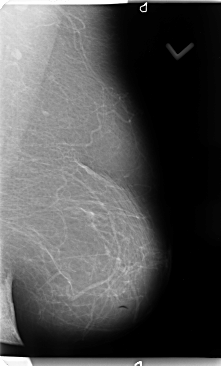

B_3135_1.RIGHT_MLO

RIGHT_MLO LINES 4696 PIXELS_PER_LINE 2712 BITS_PER_PIXEL 12 RESOLUTION 50 OVERLAY